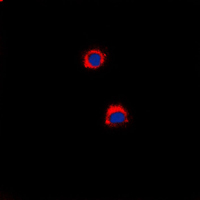

Immunofluorescent analysis of CD40 staining in A431 cells. Formalin-fixed cells were permeabilized with 0.1% Triton X-100 in TBS for 5-10 minutes and blocked with 3% BSA-PBS for 30 minutes at room temperature. Cells were probed with the primary antibody in 3% BSA-PBS and incubated overnight at 4 °C in a humidified chamber. Cells were washed with PBST and incubated with a DyLight 594-conjugated secondary antibody (red) in PBS at room temperature in the dark. DAPI was used to stain the cell nuclei (blue).